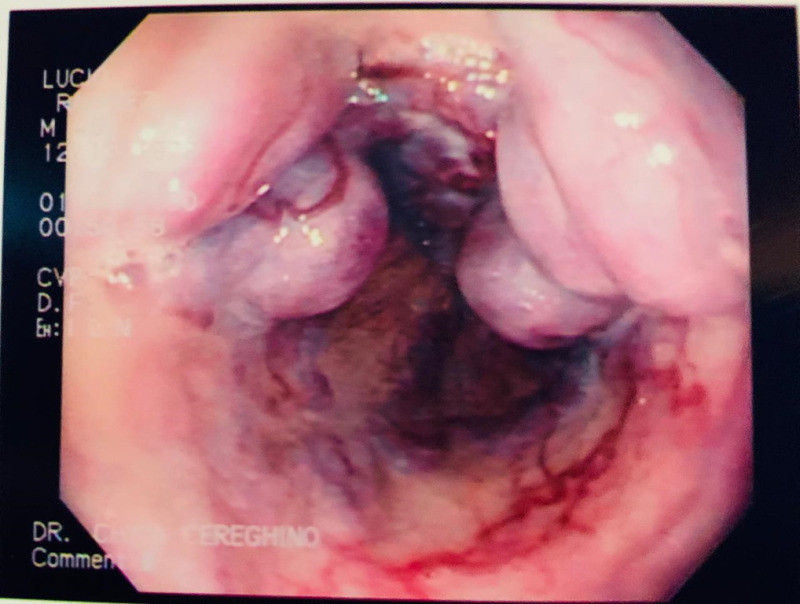

Prótesis esofágica